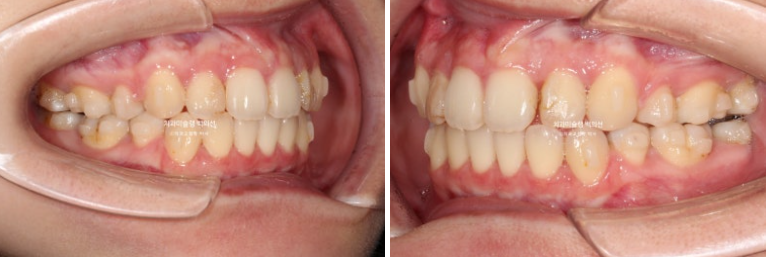

23년 7월 교정치료를 위해 내원한 20대 환자분입니다.

앞니는 가지런한 편이며 중심선도 거의 맞습니다.

교합은 좋은 상태이고

치열도 꽤 가지러한 편입니다.

거미스마일도 심한 편이었으며 돌출과 거미스마일 해소를 위해 작은어금니 4개를 발치하고 치료에 들어갔습니다.

치료방법은 인비절라인 선택하셨고 첫 세트 장치는 85개가 나왔습니다.